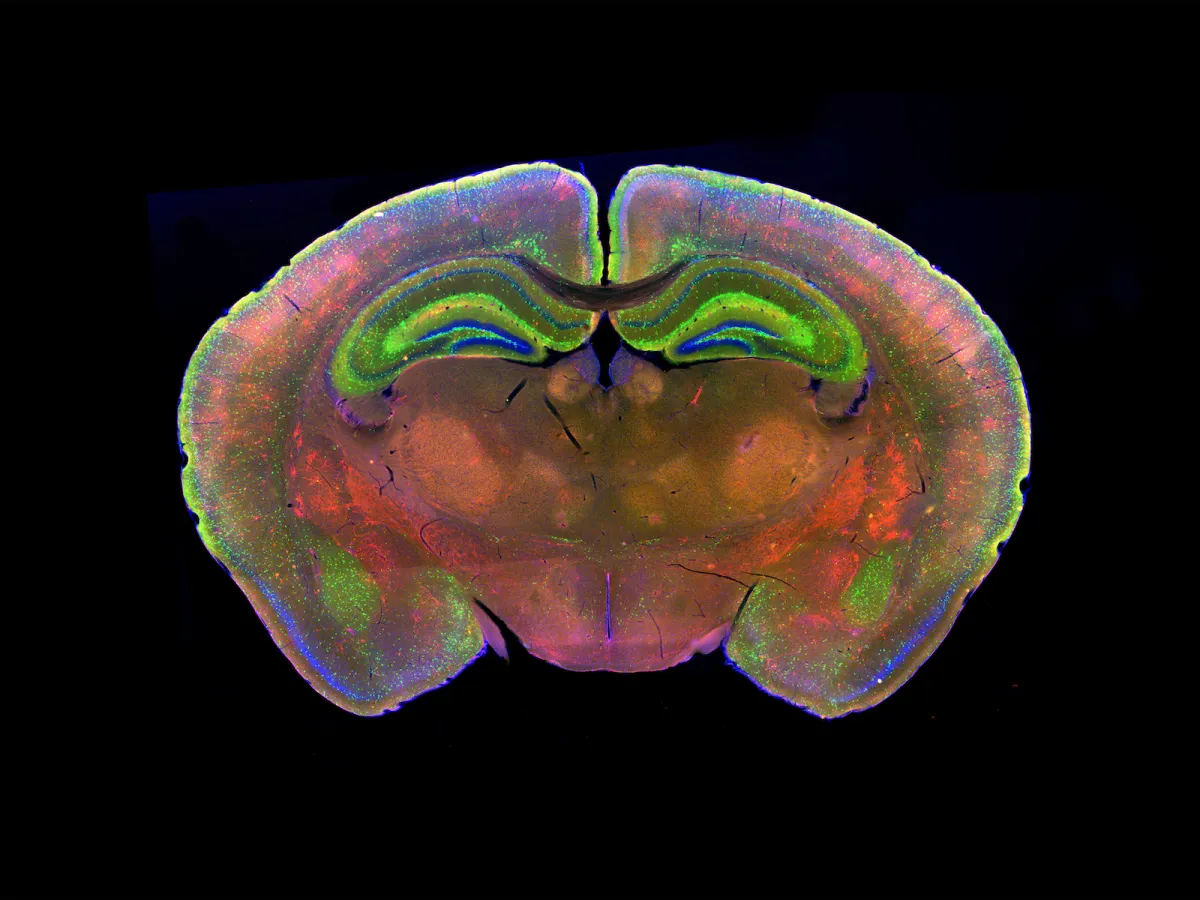

Il faut, pour cela, entrer dans quelques considérations génétiques. Les gènes de vulnérabilité aux troubles psychiques se trouvent dans les régions du génome qui divergent entre l’homme de Néandertal et Homo Sapiens, comme s’ils nous avaient accompagnés – nous Homo Sapiens – au cours de l’évolution. Ces gènes sont liés à ce que nous sommes, à la puissance de notre cerveau. Mais cette complexité a un prix : par moment, ça déraille ! Des études montrent que le cerveau humain encode les informations de façon moins robuste que celui du singe. Ce code cérébral est chez nous plus fragile mais il contient beaucoup plus d’informations. Nous avons choisi la complexité plutôt que la robustesse.

Exactement ! Du point de vue des neurosciences, on peut considérer que l’évolution a poussé au plus loin la puissance du cerveau et la machine a parfois des ratés, des faiblesses. La grande particularité du fonctionnement humain est que nous sommes capables de penser le monde. Ce n’est pas le réel que nous manipulons mais les représentations du réel. Le tableau de Magritte La trahison des images, représentant une pipe sous laquelle il est écrit « Ceci n’est pas une pipe » ne dit pas autre chose, mettant en lumière les pièges de notre représentation. Quand on pense, on perd contact avec le réel, on l’abandonne. Se représenter le monde, c’est l’enrichir à sa façon en créant et en pensant, mais il est aussi possible de se perdre. La maladie mentale est sans doute cela. Perdre pied, délirer au sens étymologique du terme, s’écarter du sillon. Cette faculté à recréer le monde par la pensée produit parfois le meilleur : l’art, les sciences, toute forme de création. Elle est aussi notre talon d’Achille, via les troubles psychiques.